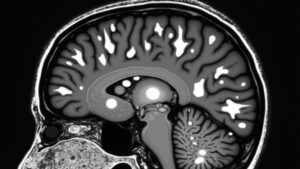

Though MRI scans can be complex, the FLAIR sequence makes certain brain conditions easier to locate. Fluid-attenuated inversion recovery (FLAIR) is an advanced MRI imaging technique that suppresses the signal from cerebrospinal fluid (CSF), helping highlight abnormalities near brain surfaces.

Unlike T1-weighted imaging, FLAIR uses a specific inversion pulse to darken CSF, improving contrast for lesions that might blend in with fluid. This sequence excels in detecting subtle changes, like those in acute stroke or meningitis, where traditional methods could fall short.

While T2-weighted images can miss subtle details, FLAIR enhances sensitivity, especially when combined with contrast-enhanced scans. By reducing CSF interference, radiologists gain clearer views of abnormalities, making FLAIR a critical tool in neuroimaging. Its precision aids in timely diagnosis, guiding better treatment decisions.

Comprehending whenever FLAIR hyperintensities signify genuine neurological concerns—rather than imaging peculiarities—assists doctors in making better decisions for patients. The FLAIR sequence shows bilateral white matter abnormalities on magnetic resonance imaging, helping diagnose conditions like multiple sclerosis or ischemic strokes. These hyperintense areas stand out against suppressed cerebrospinal fluid (CSF) signals, making lesions easier to spot.